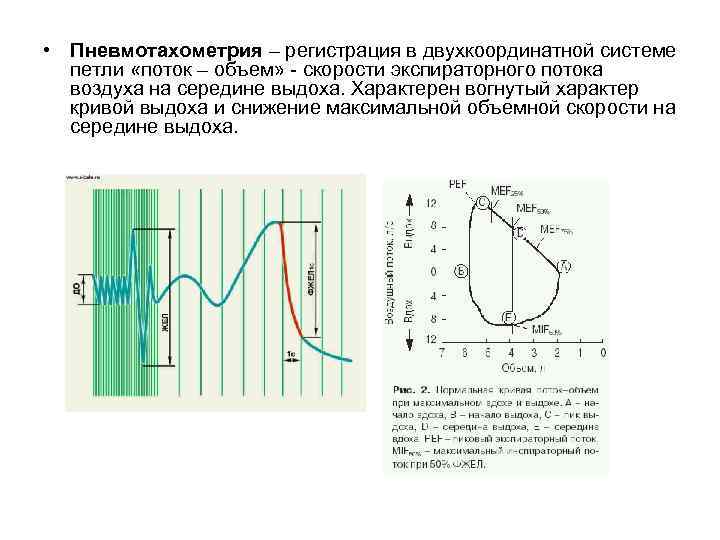

• Пневмотахометрия – регистрация в двухкоординатной системе петли «поток – объем» - скорости экспираторного потока воздуха на середине выдоха. Характерен вогнутый характер кривой выдоха и снижение максимальной объемной скорости на середине выдоха.